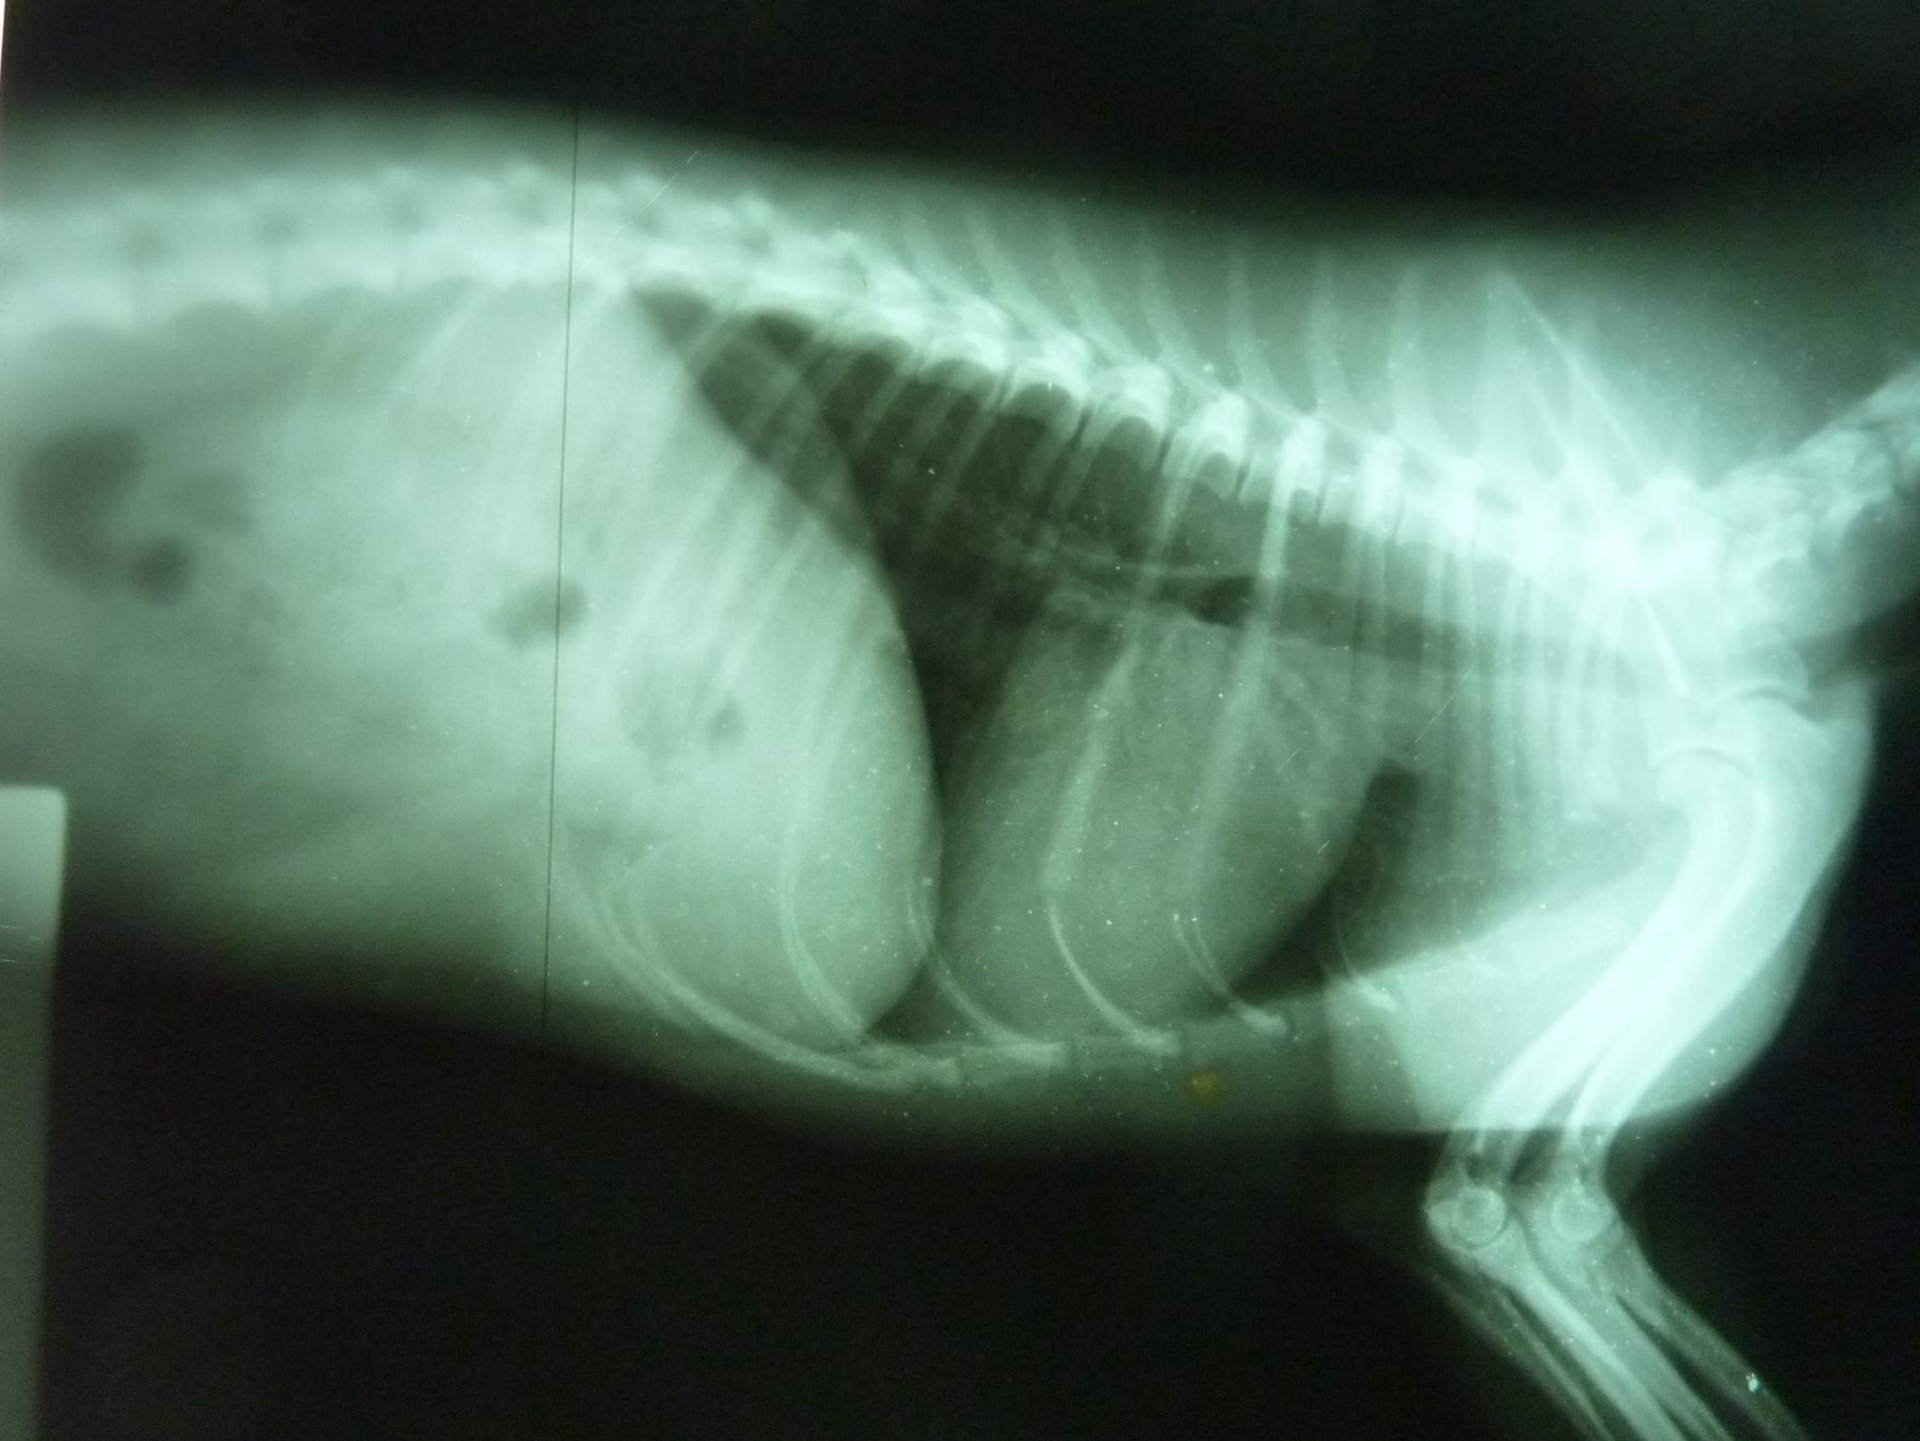

Diagnostic précis sans examens superflus

Médecine interne : le plus souvent, l’examen clinique est suffisant, sans recours systématique aux examens complémentaires.

Toutefois, les cas complexes sont reconnus comme tels voire sont référés à un centre spécialisé.